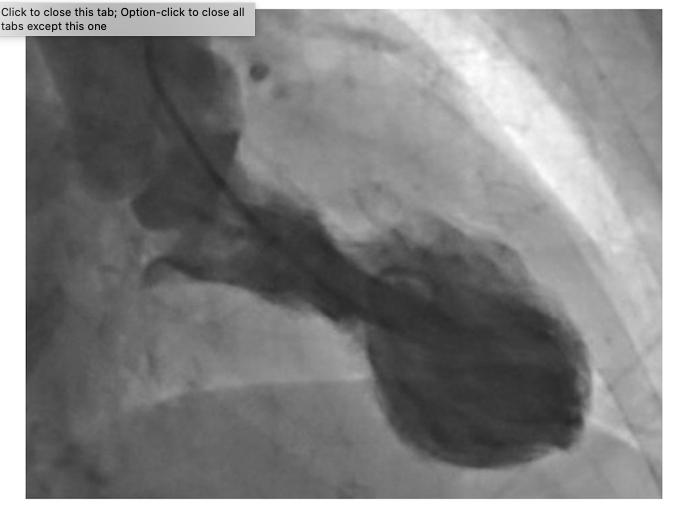

TTS, also known as "broken heart" syndrome, is characterised by a sudden temporary weakening of the heart muscles that causes the left ventricle of the heart to balloon out at the bottom while the neck remains narrow, creating a shape resembling a Japanese octopus trap, from which it gets its name. Since this relatively rare condition was first described in 1990, evidence has suggested that it is typically triggered by episodes of severe emotional distress, such as grief, anger or fear, or reactions to happy or joyful events. Patients develop chest pains and breathlessness, and it can lead to heart attacks and death. TTS is more common in women with only 10% of cases occurring in men. [2]